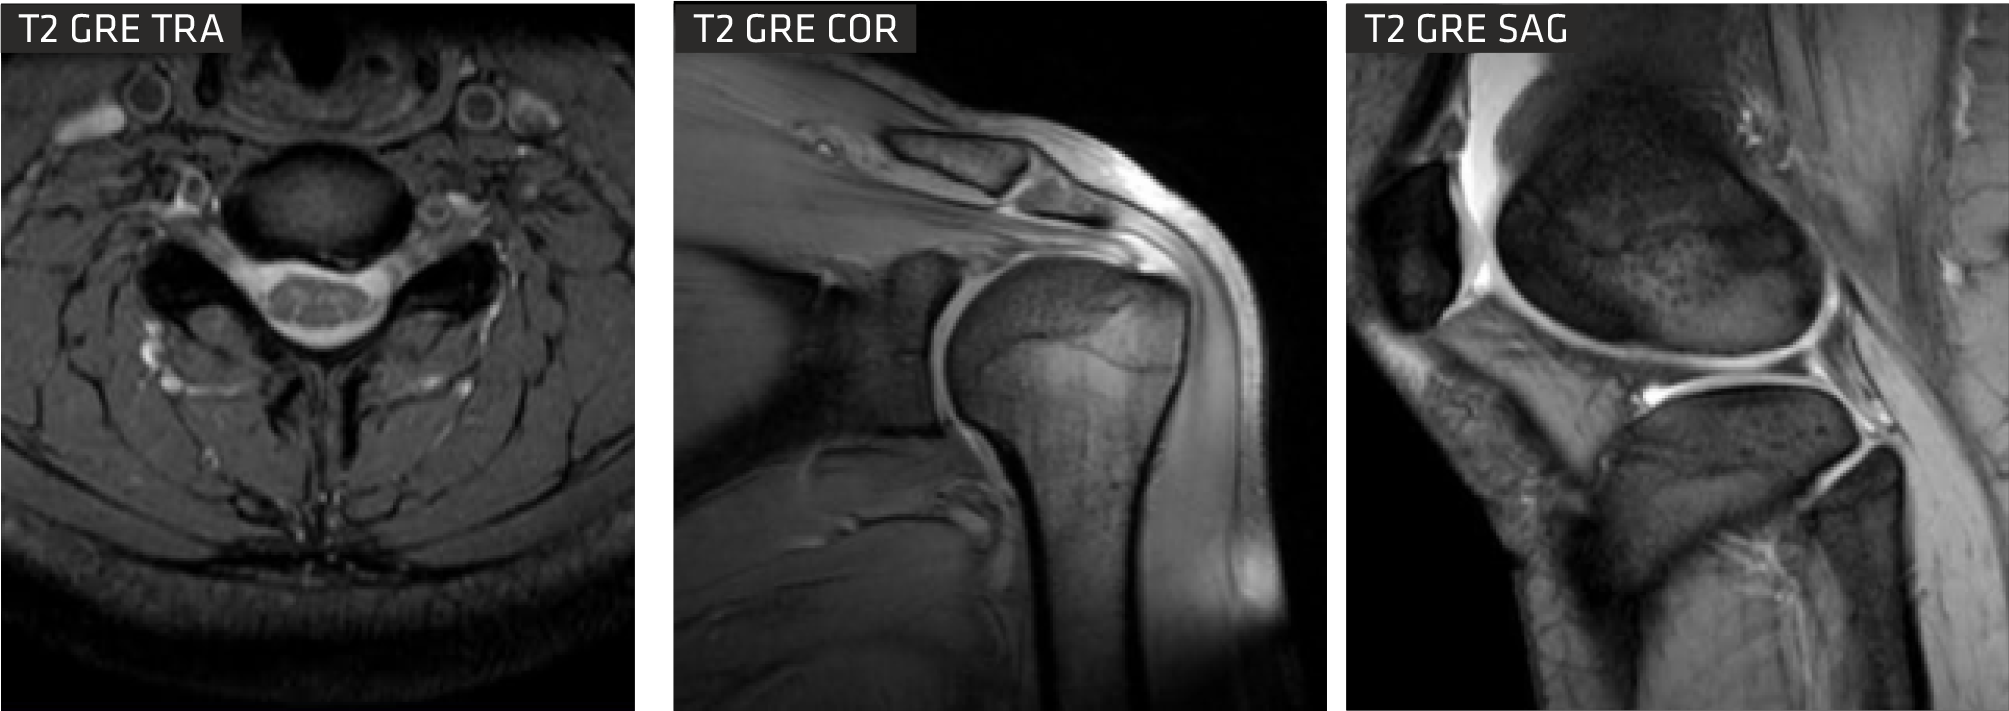

With advancements in MSK sequences, RF coils, computing technology and optimized magnet homogeneity, Clarity delivers high resolution musculoskeletal(MSK) images. This imaging technique enables you to image bone, joint and muscular soft tissue with remarkable tissue contrast.

Cartilage Quantification provides quantitative assessment of cartilage composition to track the degradation of tissues in the early stages of multiple pathologies? within joints, which can't be detected by conventional imaging techniques. It allows for non-invasive measurement of collagen content.

Specifically crafted for imaging the neck and cervical spine, this technique aims to fully eliminate pulsation artifacts.